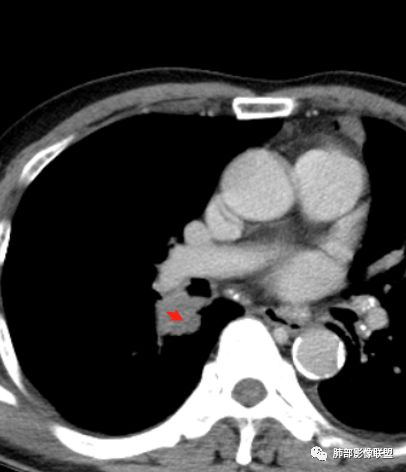

膈面上还有一个结节

左肺上叶病灶长轴与支气管走形一致,提示沿支气管分布病变,倾向于炎性,大家可能怀疑这个病例是来源于胸膜下为主的,胸膜下来源首先整体是来源于胸膜下,与胸膜下之间没有间隙,而这例与胸膜下有间隙。而且这个病变是沿支气管朝外蔓延的,而胸膜下来源的是朝内蔓延的,唯一给我们错觉的是靠近纵隔胸膜这个地方有问题。但是靠近纵隔胸膜这个位置实变不是靠近胸膜实变,它边缘收缩的,没有膨隆的迹象。我们看到里面支气管直达远端稍扩张,是以中央间质为主、小叶间隔朝外蔓延,有间质也有实质病变,走向是沿中央间质方向走的,我个人倾向炎性病变。    问题是右下叶病灶怎么解释?右隔上、右肺门各有一个结节。这个病人有急性咳嗽、胸痛的病史,还有糖尿病病史,周围渗出比较明显,应该警惕炎性病变,要警惕克雷伯杆菌、结核、金葡菌霉菌,因为糖尿病人经常好发这些病菌感染。那么右下叶病变怎么考虑?能不能一元论?    左肺病灶是一个急性渗出为主的病变,一个急性感染的迹象;右肺下叶背段结节,没有看到支气管,增强图支气管壁增厚,局部小结节,呈分叶状,支气管堵塞,没有粘液栓样指套样改变,但是里面有强化,我倾向于癌,其次待排结核。我还是倾向于癌的可能性,恶性可能性大一些,可惜我看不到支气管腔内。还考虑有没有淀粉样变性的问题,弥漫钙化灶最常见的一个是结核,另一个是淀粉样变性。叶段支气管壁有弥漫增厚的迹象。所以淀粉样变性跟结核都要考虑。

1.右肺下叶支气管壁增厚,后壁为主,且显示壁外结节,未见异常强化。这样的结节和蔓延方式一般会高度怀疑气道来源的恶性肿瘤,如鳞癌、粘液表皮样癌、腺样囊性癌等。可惜没有相应病理学资料支持。

右肺下叶近膈面球形病灶缺乏恶性病灶特点,没有分叶、毛刺、牵拉等,应当符合炎性。